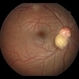

- Fundus camera

- Fundus photograph of a 72-year-old man with a retinal astrocytoma of the left eye.